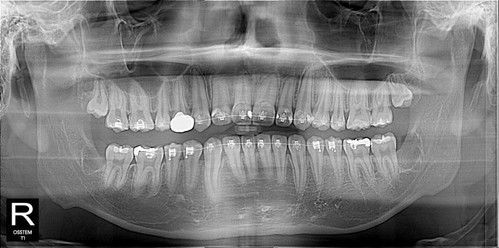

우측 구치부 교합이 좋지 않아 교정을 시작했고 교정을 하면서 치아이동을 위해 사랑니 발치를 해야했다...

좌측 매복정도가 깊어 한쪽씩 뽑아야한다고 얘기했지만

수면 마취가 효과가 잘 유지되었고 시간상 괜찮아 우측도 그 날 발치를 완료^^